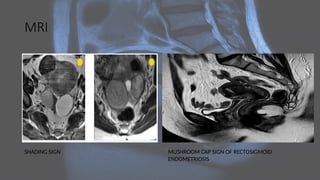

MRI

SHADING SIGN MUSHROOM CAP SIGN OF RECTOSIGMOID

ENDOMETRIOSIS

MRI SHADING SIGN MUSHROOMCAP SIGN OF RECTOSIGMOID ENDOMETRIOSIS